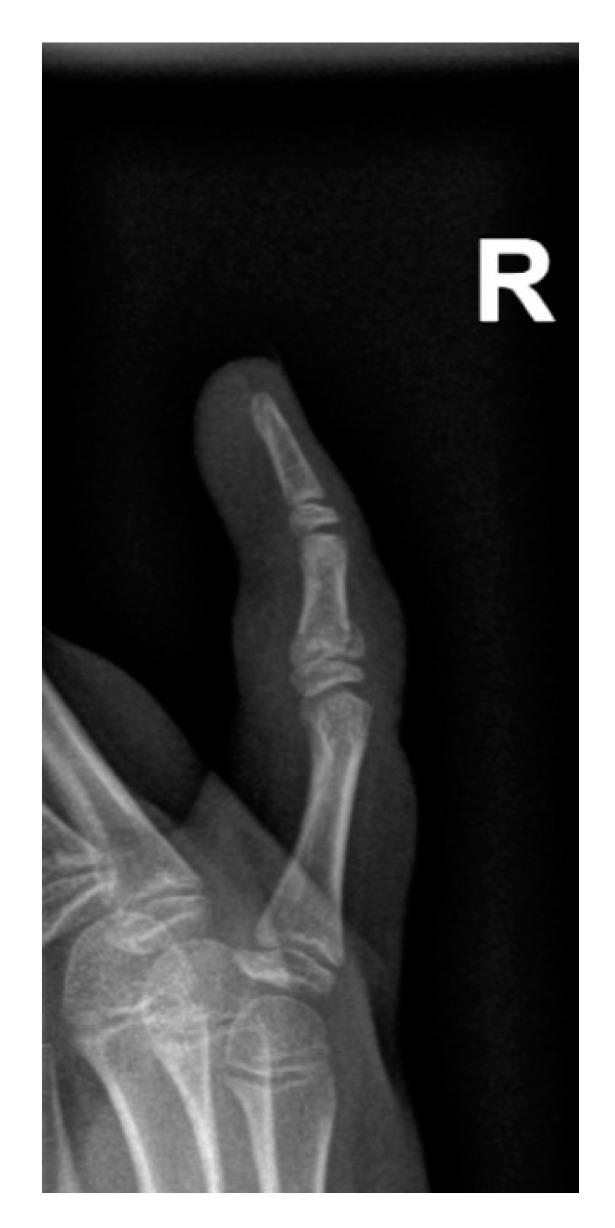

波兰西里西亚儿科人群手部损伤-创伤后 X 射线的探索性横断面研究。

Hand Injuries in the Polish Silesian Paediatric Population-An Exploratory Cross-Sectional Study of Post-Traumatic X-rays.

In the paediatric population, hand injuries are one of the most frequent injuries and the second most frequent area of fracture. It is estimated that hand injuries account for up to 23% of the trauma-related causes of emergency department visits. Not only are they a significant factor in health care costs, but they may also lead to detrimental and long-term consequences for the patient. The discrepancy observed between the published studies suggests a geographical variation in their epidemiology. The aim of this study is to determine the localisation of injuries and fractures involving the hand in the paediatric population of the Polish Silesia region. This exploratory cross-sectional study involved 1441 post-traumatic hand X-ray examinations performed at the Department of Diagnostic Imaging of the John Paul II Upper Silesian Child Health Centre in Katowice between January and December 2014. The study group consisted of 656 girls and 785 boys who were 11.65 ± 3.50 and 11.51 ± 3.98 years old, respectively (range: 1-18 years). All examinations were evaluated for the location of the injury and presence of fracture(s). Finger injuries were dominant ( = 1346), with the fifth finger being the most frequently injured ( = 381). The majority of injuries were observed among children who were 11 years old ( = 176), with a visible peak in the 11- to 13-year-old group. A total of 625 bone fractures were detected. Fractures of the proximal phalanges ( = 213) and middle phalanges ( = 159) were most common, and fifth finger ( = 189) predominance was again observed. A gender-independent positive correlation was found between patients' age and finger injuries ( < 0.01) as well as metacarpal injuries ( < 0.01). There was no correlation between patients' age and fractures in these locations ( > 0.05). Metacarpal injuries ( < 0.01), finger injuries ( < 0.01), fractures ( = 0.01), and fractures with displacement ( = 0.03) were more common among males regardless of age. The results indicate that 11-year-old boys are at an increased risk of hand injuries and fractures. The distal and middle phalanges of the right hand, especially of the fifth digit, were the most susceptible to fracture localisation. Thus, injuries in these areas should be perceived as most likely to cause fractures and therefore demand careful examination.

在儿科人群中,手部损伤是最常见的损伤之一,也是第二常见的骨折部位。据估计,手部损伤占急诊科因创伤相关原因就诊的比例高达 23%。它们不仅是医疗保健费用的重要因素,还可能对患者造成长期的不利影响。发表的研究之间存在差异,表明其流行病学存在地域差异。本研究旨在确定波兰西里西亚地区儿科人群手部损伤和骨折的部位。这是一项探索性的横断面研究,共纳入了 2014 年 1 月至 12 月期间在卡托维兹的约翰·保罗二世上西里西亚儿童保健中心放射科进行的 1441 例手部创伤后 X 射线检查。研究组包括 656 名女孩和 785 名男孩,他们的年龄分别为 11.65 ± 3.50 岁和 11.51 ± 3.98 岁(年龄范围:1-18 岁)。所有检查均评估了损伤部位和骨折情况。手指损伤占主导地位(= 1346),第五指受伤最常见(= 381)。大多数损伤发生在 11 岁的儿童中(= 176),11-13 岁年龄组的损伤发生率最高。共发现 625 例骨骨折。掌骨(= 213)和中节指骨(= 159)骨折最常见,再次观察到第五指(= 189)优势。患者年龄与手指损伤(<0.01)和掌骨损伤(<0.01)之间存在独立的正相关关系。患者年龄与这些部位的骨折之间无相关性(>0.05)。无论年龄大小,男性的掌骨损伤(<0.01)、手指损伤(<0.01)、骨折(= 0.01)和有移位的骨折(= 0.03)更为常见。结果表明,11 岁男孩手部受伤和骨折的风险增加。右手的远节和中节指骨,尤其是第五指,最容易发生骨折。因此,这些部位的损伤应被视为最有可能导致骨折,因此需要仔细检查。